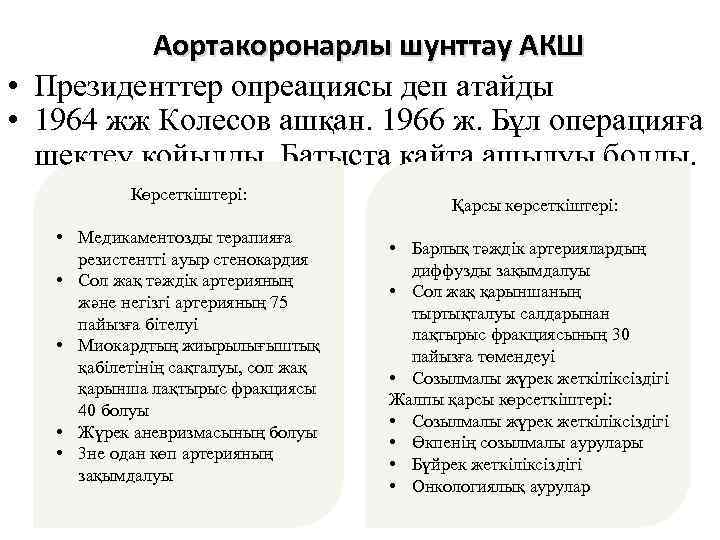

Аортакоронарлы шунттау АКШ • Президенттер опреациясы деп атайды • 1964 жж Колесов ашқан. 1966 ж. Бұл операцияға шектеу қойылды. Батыста қайта ашылуы болды. Көрсеткіштері: • Медикаментозды терапияға резистентті ауыр стенокардия • Сол жақ тәждік артерияның және негізгі артерияның 75 пайызға бітелуі • Миокардтың жиырылығыштық қабілетінің сақталуы, сол жақ қарынша лақтырыс фракциясы 40 болуы • Жүрек аневризмасының болуы • 3 не одан көп артерияның зақымдалуы Қарсы көрсеткіштері: • Барлық тәждік артериялардың диффузды зақымдалуы • Сол жақ қарыншаның тыртықталуы салдарынан лақтырыс фракциясының 30 пайызға төмендеуі • Созылмалы жүрек жеткіліксіздігі Жалпы қарсы көрсеткіштері: • Созылмалы жүрек жеткіліксіздігі • Өкпенің созылмалы аурулары • Бүйрек жеткіліксіздігі • Онкологиялық аурулар

Аортакоронарлы шунттау АКШ • Президенттер опреациясы деп атайды • 1964 жж Колесов ашқан. 1966 ж. Бұл операцияға шектеу қойылды. Батыста қайта ашылуы болды. Көрсеткіштері: • Медикаментозды терапияға резистентті ауыр стенокардия • Сол жақ тәждік артерияның және негізгі артерияның 75 пайызға бітелуі • Миокардтың жиырылығыштық қабілетінің сақталуы, сол жақ қарынша лақтырыс фракциясы 40 болуы • Жүрек аневризмасының болуы • 3 не одан көп артерияның зақымдалуы Қарсы көрсеткіштері: • Барлық тәждік артериялардың диффузды зақымдалуы • Сол жақ қарыншаның тыртықталуы салдарынан лақтырыс фракциясының 30 пайызға төмендеуі • Созылмалы жүрек жеткіліксіздігі Жалпы қарсы көрсеткіштері: • Созылмалы жүрек жеткіліксіздігі • Өкпенің созылмалы аурулары • Бүйрек жеткіліксіздігі • Онкологиялық аурулар